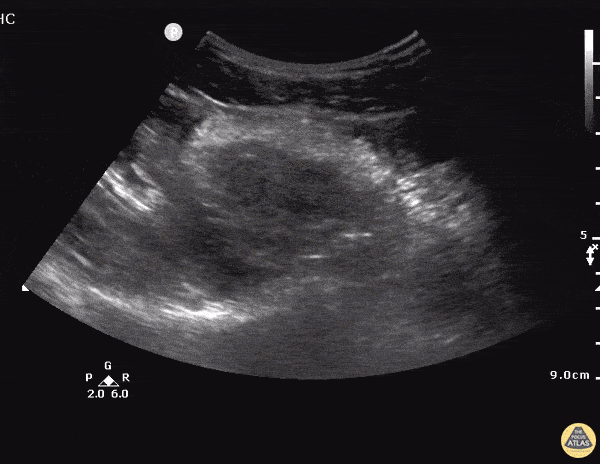

OB/Gyn - Ectopic - Ruptured Cornual Ectopic Pregnancy - Longitudinal

24 y/o F presents after a brief syncopal episode. Endorses heavy vaginal bleeding for 2 weeks. On exam, tachycardic and tender to palpation in lower abdomen. Urine HCG was positive. Transabdominal longitudinal sonogram view of the pelvis showed a large hypoechoic collection suggestive of free pelvic fluid in the proximity of a solid hyperechoic mass in the left adnexal. Just inferior to the mass is the uterus a small amount of hypoechoic fluid in the endometrium but no clear intrauterine pregnancy. GYN was consulted immediately and the ultimate operative note for this patient described a ruptured cornual ectopic pregnancy. A cornual pregnancy or interstitial pregnancy is a type of ectopic pregnancy located outside of the uterine cavity in the distal fallopian tube as it penetrates into the muscular wall of the uterus. This type of ectopic pregnancy has the potential to grow to larger sizes than standard tubal ectopic pregnancies and carries a higher mortality risk. Dr. Tareq Azad and Dr. Scott Kendall - Kings County Emergency Medicine